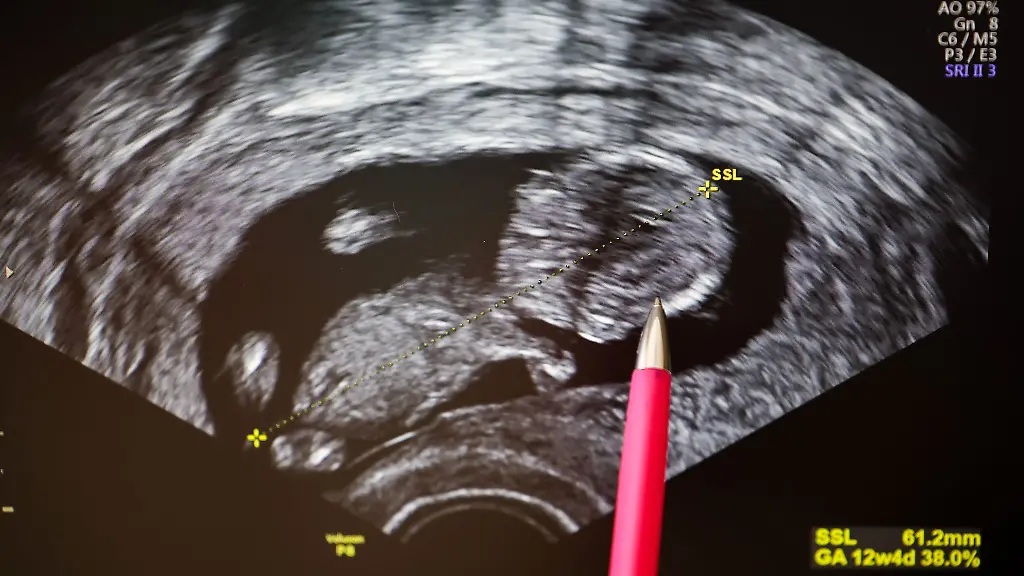

Trinkt eine Schwangere Alkohol, kann das lebenslange Schäden für ihr Kind nach sich ziehen. In Sachsen betrifft das laut Ministerium jedes Jahr Hunderte Neugeborene.

Dresden (dpa/sn) - Gesundheitsministerin Petra Köpping (SPD) hat an schwangere Frauen appelliert, auf Alkohol zu verzichten. Ansonsten drohten unheilbare Schäden für das Kind, sagte sie mit Blick auf den Tag des alkoholgeschädigten Kindes, der an diesem Montag begangen wird. Experten sprechen von fetalen Alkoholspektrumstörungen (FASD). Laut Ministerium werden jedes Jahr 500 bis 600 Kinder in Sachsen mit FASD geboren; bundesweit sind es etwa 10 000 Neugeborene.